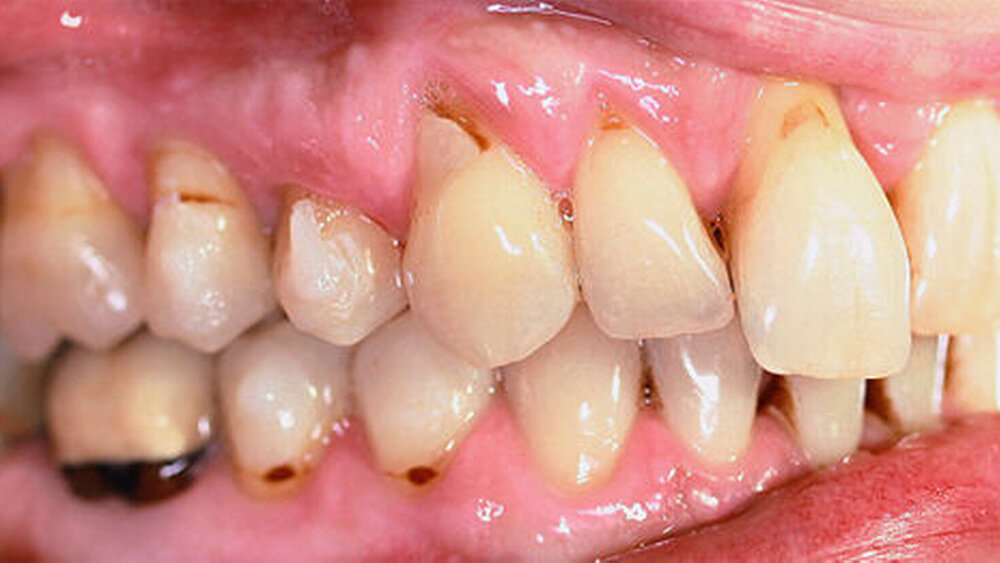

Röntgenologisch stellte sich im Orthopantomogramm der bereits intraoral ersichtliche horizontale und vertikale Knochenabbau mit Attachmentverlust an einzelnen Zähnen dar. Die Erhaltungswürdigkeit einzelner Zähne war aufgrund des starken Knochenverlustes beziehungsweise der Beeinträchtigung des Halteapparates als kritisch zu beurteilen.

Zudem wurde die Diagnose einer Parodontitis gestellt, die eine Rücküberweisung an den Hauszahnarzt erforderlich machte (Abbildung 2).